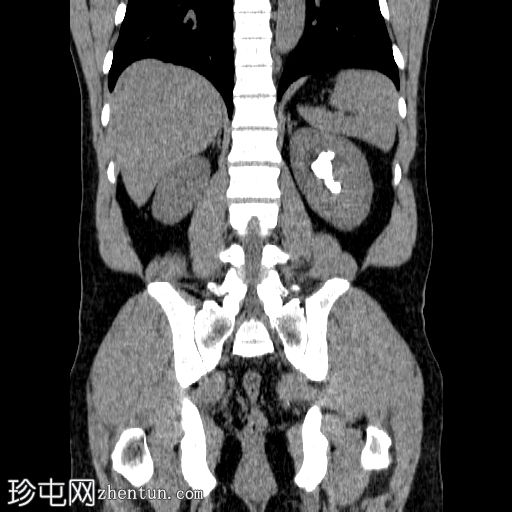

冠状位

平扫

左侧肾盂内可见一鹿角状结石,延伸至肾盏系统,平均CT值约为1200 HU。

右肾可见数枚微小结石,最大一枚位于肾下盏,直径约2 mm。这些结石未引起任何梗阻性改变。

本病例展示了左肾鹿角状结石的典型

影像

学表现。